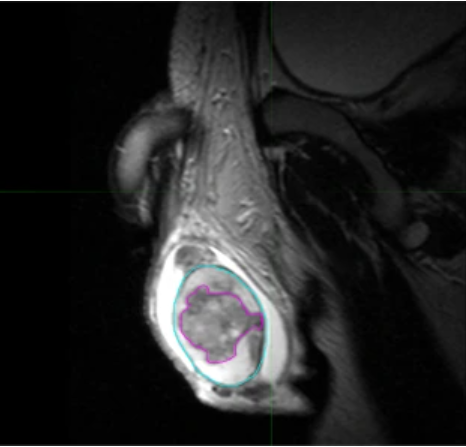

Una imagen de resonancia magnética en blanco y negro que muestra un umor de testículo, resaltado en rosa.

Tumor de testículo, resaltado en rosa, en una imagen por resonancia magnética.

Fuente: Scientific Data. Agosto de 2021. https://doi.org/10.1038/s41597-021-00990-z. CC BY 4.0.